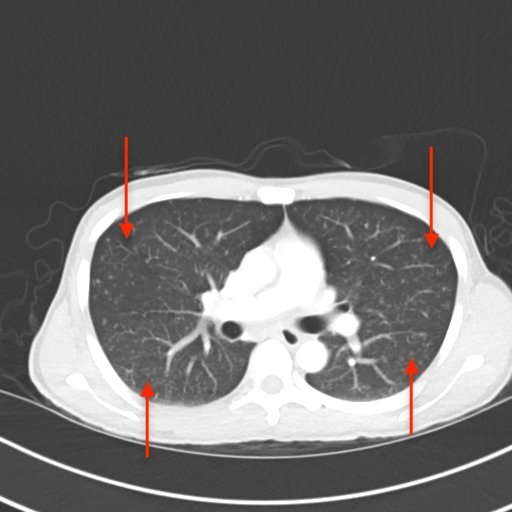

Miliary TB, CT, Annotated. JETem 2020

A Case Report on Miliary Tuberculosis in Acute Immune Reconstitution Inflammatory Syndrome